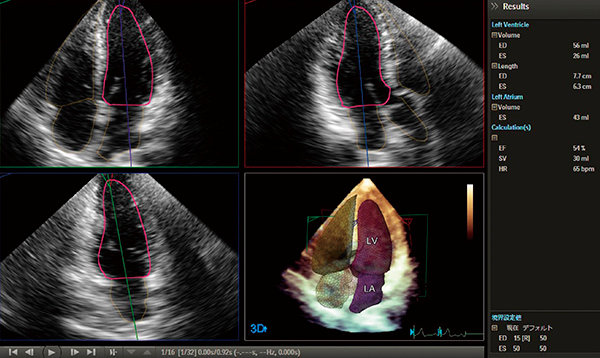

HeartModelA.I.は,心臓の3D容積計測の自動化を実現したソフトウェアである(図6)。従来のディスク総和法では,左室,左房容積計測で計6断層をトレースする必要があった。HeartModelA.I.は,心尖部の4腔像を描出し,3D画像を取得して,解析ボタンを押す。それだけで,左心室の拡張・収縮期,左房容積の計測を行うことができるツールである。内部では腔内認識,形状認識,部位の識別などを自動で行い,容積を計測,表示する。3Dでの計測であるため,腔内の形状に依存しない計測が可能である。

解析が自動化されることで,従来の3D解析ソフトウェアで必要だった多くの工程が簡略化され,短時間で結果を得られる。また,得られた結果の検者間誤差もなくなるため,計測結果の安定が期待される。

図6 3D自動容積解析ソフトウェアHeartModelA.I.